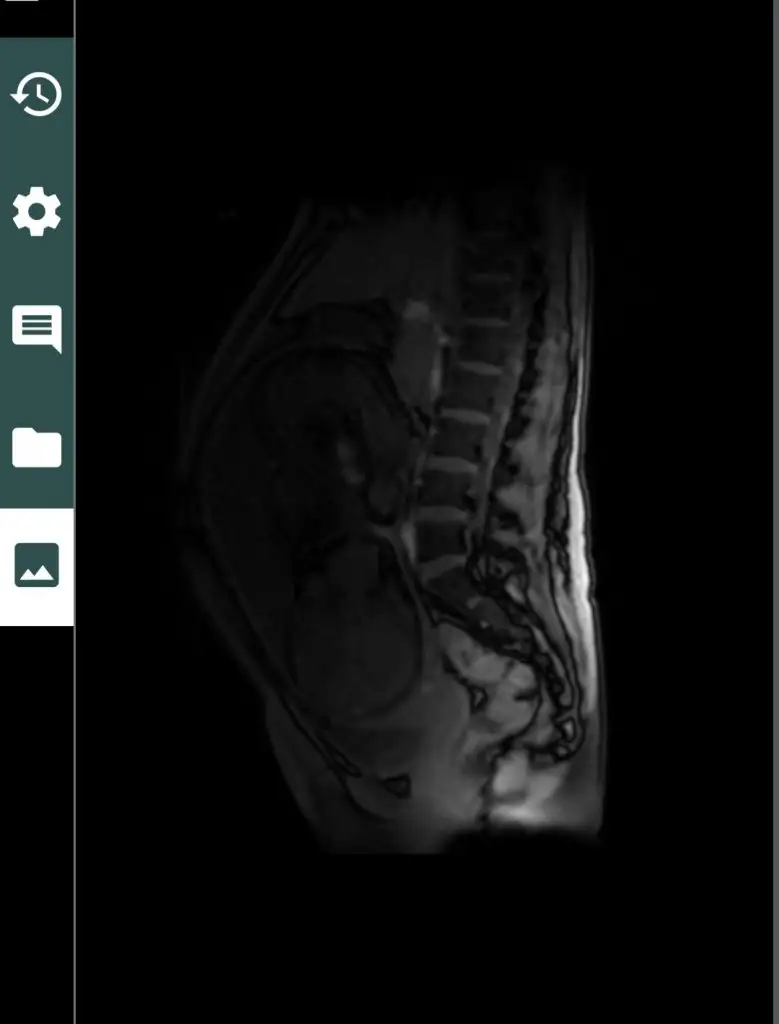

YEKTA61 erken doğum riskin devam ediyor sanırım inşallah seninkide en azından 37 i falan bekler canım ya.

Bizde 35+3 te gideceğiz bi daha doktorumuza daha 2 hafta var

Şaka maka günlerimiz yaklaşıyor kızlartakvimde 34 yazdıgına inanamıyorum